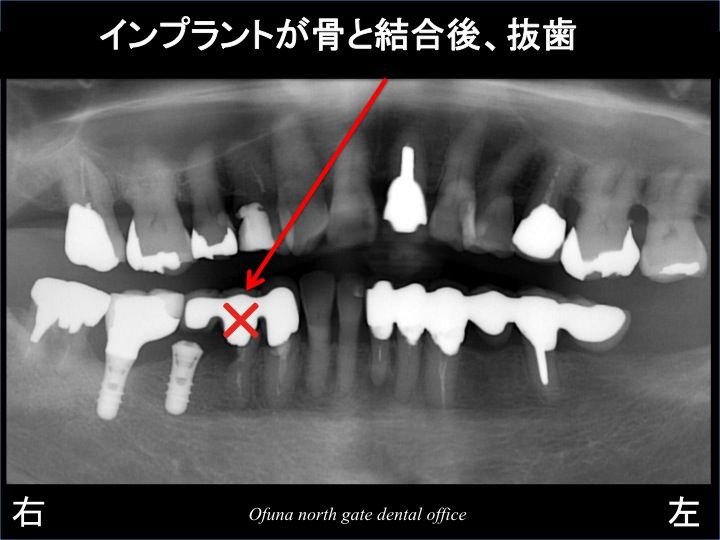

以下は、奥の欠損部にインプラントを1本埋入した直後です。

そして、インプラント手術直後には、取れたセラミックを仮歯として使用しました。

インプラントと骨が結合(くっつく)後、手前の歯を抜歯します。

そして、抜歯と同時にインプラントを土台とした仮歯に変更するのです。